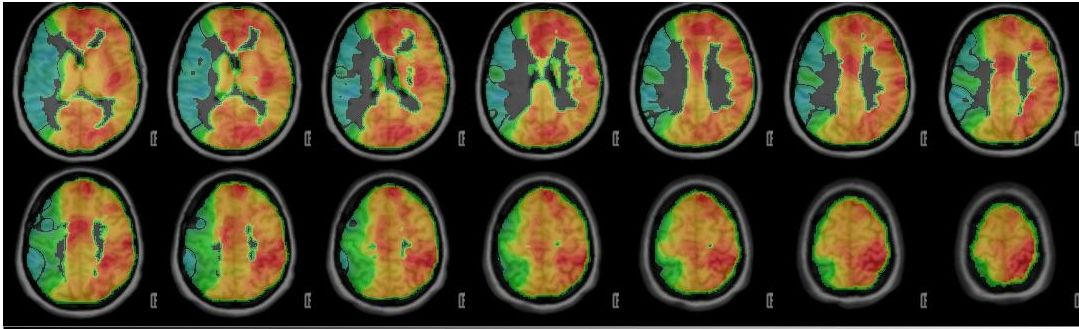

PET-CT nach Diamox Gabe

PET-CT nach Diamox Gabe zeigt eine einseitig deutlich reduzierte Perfusionsreserve (grüne Farben) im Vergleich zur Gegenseite mit ausreichendem Anstieg der Durchblutung (warme Farben).